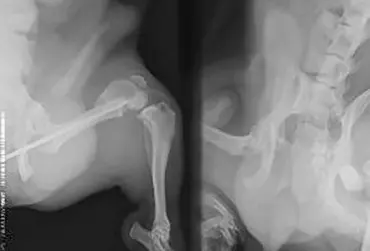

Opisywany przypadek dotyczy 4-letniego psa, samca, rasy pekińczyk. W innym zakładzie leczenia zwierząt wykonano zabieg osteosyntezy lewej kości udowej za pomocą pojedynczego gwoździa śródszpikowego. Pacjent trafił do przychodni w celu konsultacji ortopedycznej z powodu braku efektów leczenia. Badanie radiologiczne uwidoczniło przebudowę kości udowej oraz wytworzenie stawu rzekomego z miejscu przełomu. Wykonano zabieg osteosyntezy z użyciem płyty L blokowanej 2,7 mm oraz przeszczepu istoty gąbczastej z kości ramiennej.